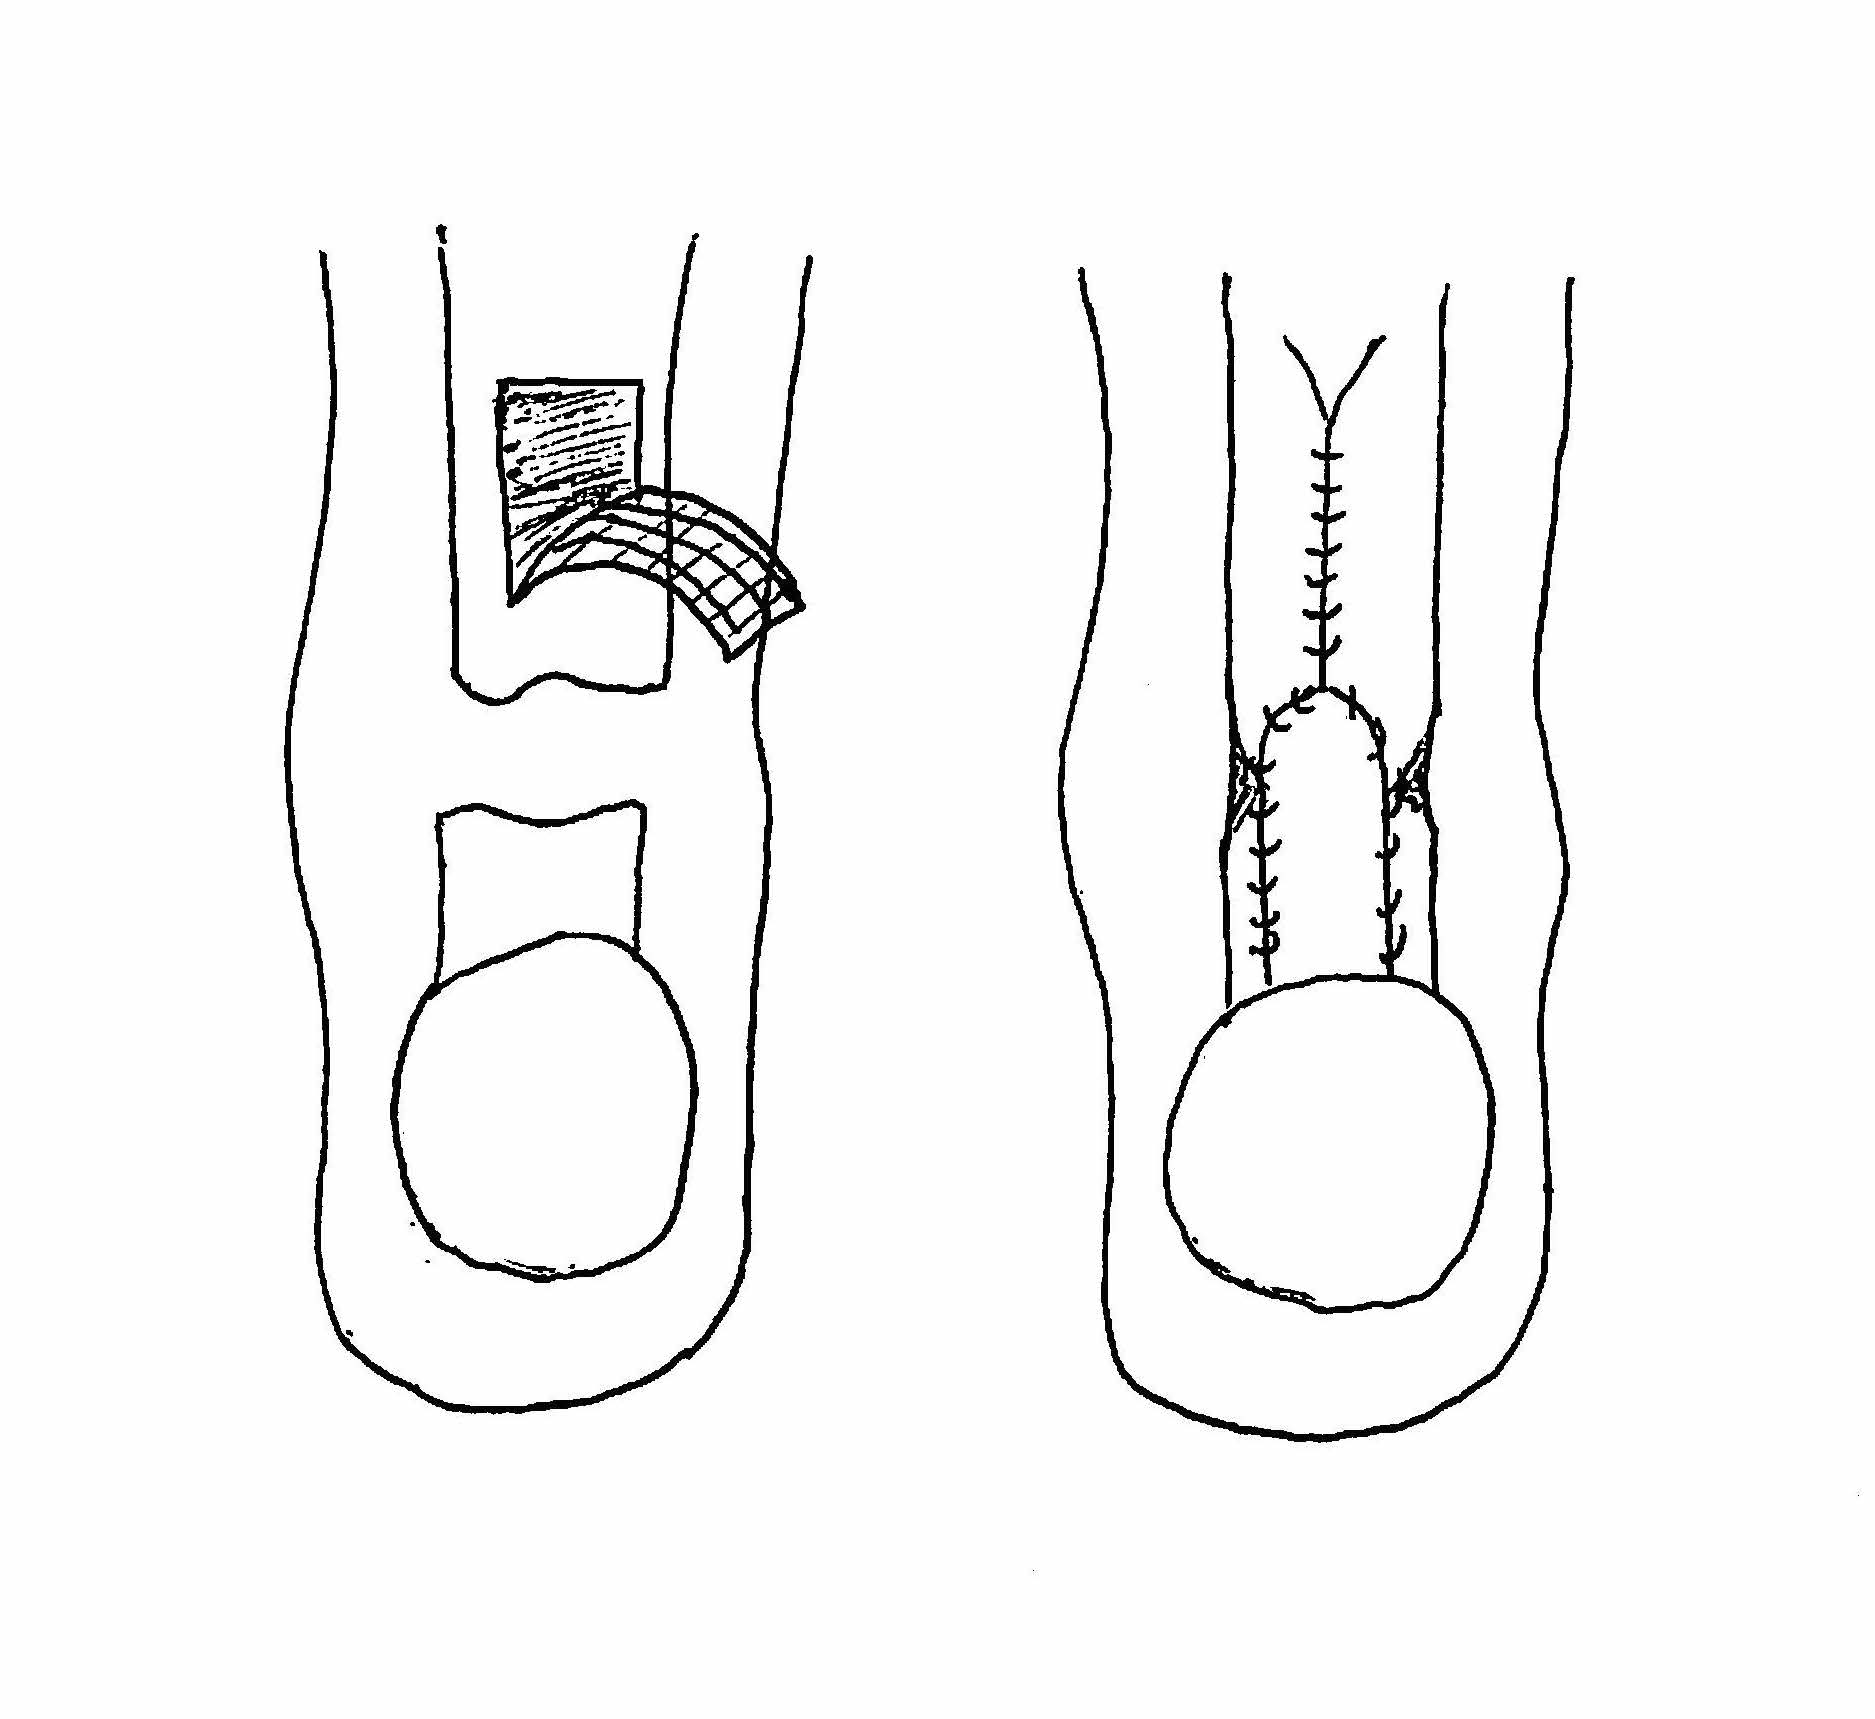

Turndown

Technique

Bosworth technique

- harvest central third fascia

- from musculotendinus junction as far proximal as possible

- leave attached distally, detach proximally

- closure fascia above

- tubularise fascia with 2.0 ethibond

- drill hole through calcaneal tuberosity

- pass through calcaneum

- suture to itself